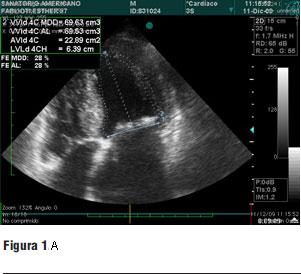

Dados los resultados de los estudios previos se entendió que el paciente era pasible de implante percutáneo de prótesis válvular aórtica autoexpandible CoreValve®. El 9 de marzo de 2010 se realizó el implante en el laboratorio de hemodinamia. Se realizó profilaxis con cefalosporinas. Previo al procedimiento se realizó anestesia general con IOT y ARM, colocación de sonda transesofágica de ecocardiograma, colocación de marcapaso transitorio en ventrículo derecho por vía subclavia izquierda, VVC y punción arterial femoral izquierda para introducción de catéter pigtail 6 F que sirvió para realizar aortograma, medir gradientes y controlar posicionamiento de prótesis valvular. Se colocó introductor arterial 18 F por punción femoral derecha y se realizó valvuloplastia aórtica con balón NUMED 25 x 4.0 mm con sobreestimulación simultánea a 180 cpm para evitar el desplazamiento del balón (figuras 2 y 3). A continuación se colocó la prótesis valvular aórtica CoreValve® Nº 29 a nivel del anillo valvular aórtico (figura 4). Se realizó control angiográfico y hemodinámico observándose mínima insuficiencia valvular aórtica y gradiente transvalvular de 30 mm (figura 5). Se cerró el orificio de punción arterial femoral derecha con Prostar XL®. El procedimiento se realizó con éxito clínico, angiográfico y hemodinámico. La figura 6 muestra los gradientes transvalvulares pre y postprocedimiento inmediato por ecocardiografía. Durante el mismo no hubo eventos ni complicaciones. En la evolución intrahospitalaria en CTI se constató sangrado en la zona de punción femoral derecha que requirió cierre definitivo con cirugía vascular. El 13 de marzo de 2010 se retiró el marcapaso transitorio, sin registrarse episodios de bloqueo auriculoventricular y es dado de alta de CTI a sala donde evoluciona estable. El 15 de marzo de 2010 se realizó ecocardiograma de control que mostró prótesis aórtica normofuncionante, gradiente máximo 20 mm Hg y medio 12 mm Hg y leve insuficiencia. El 16 de marzo de 2010 es dado de alta a domicilio en buenas condiciones. Se realizó control clínico a los 15 días permaneciendo estable bajo tratamiento con ácido acetilsalicílico, clopidogrel, betabloqueantes, trimetazidina y estatinas. A los 45 días del procedimiento el paciente permanece asintomático con igual tratamiento farmacológico y se controló con nuevo ecocardiograma que mostró: prótesis biológica en posición aórtica con sigmoideas normales, gradiente sistólico pico de 23 mmHg y medio de 13 mmHg, índice de obstrucción 0,43 y mínima insuficiencia perivalvular; leve hipertrofia ventricular izquierda con contractilidad global y segmentaria conservada.

Figura 3. Balón de valvuloplastia abierto a nivel de válvula aórtica.